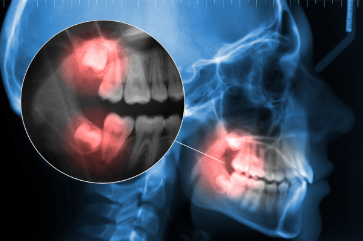

Painless Wisdom Teeth Removal: Modern Techniques for a Stress-Free Experience

Wisdom teeth removal has a reputation for being one of the more dreaded dental procedures, but thanks to modern techniques, it doesn’t have to be. Today’s oral surgeons use advanced tools, refined methods, and effective anesthesia options to ensure patients experience minimal discomfort and a smooth recovery. At Coulee Region Implants & Oral Surgery, our […]